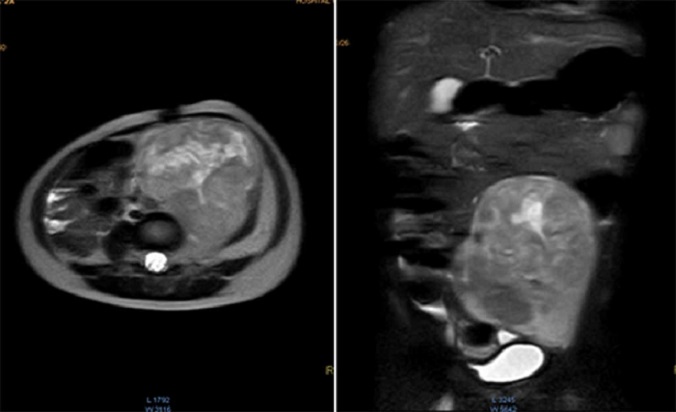

Se realizó la resonancia magnética nuclear (RMN) de abdomen contrastada previa a la resección tumoral, que mostró que la masa envolvía la arteria y vena iliaca izquierdas (Fig. 1).

Figura 1 Resonancia magnética de abdomen con contraste que muestra masa sólida de 107×80×76mm de diámetros craneocaudal, anteroposterior y transverso que ocupa hipogastrio, fosa iliaca y flanco izquierdos y gran parte del mesogastrio, pediculada desde los agujeros de conjunción L4-L5, L5-S1 y S1 izquierdos. Sólida, heterogénea, con necrosis, vascularizada, que envuelve parcialmente la bifurcación aórtica y totalmente la arteria iliaca primitiva izquierda y sus ramificaciones, al igual que la vena iliaca.